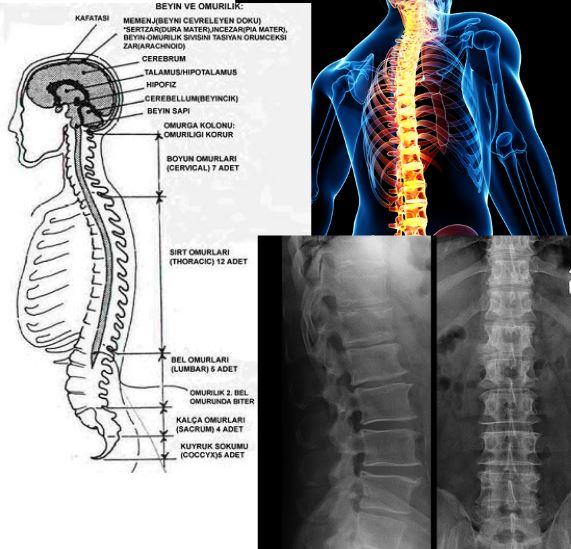

Başın alt arkasından başlayarak insanlarda ve kimi primatlarda kuyruksokumuna, kimi hayvanlarda da kuyruğun ucuna değin birbirine eklenmiş omurlardan oluşan kemik dizisidir. Omurgalı yaratıkların iskeletlerinin esasını oluşturur. İnsanda omurgayı oluşturan 33 kemiğin her birine "omur" denir. Omurların 7'si boyunda, 12'si sırtta, 5'i belde, 5'i sağrıda, 4'ü de kuyruksokumundadır. Sağrıda ve kuyruksokumundaki omurlar biçimlerini kaybedip birbirleriyle kaynaşmışlardır. Hayvanlarda omurlar kuyrukta da uzayıp gider. Her omurda kalın bir kısımla üç çıkıntı, ortada da yuvarlak bir delik bulunur. Bu kalın kısma "omur cismi", ortadaki çıkıntıya da "dikensi çıkıntı" denir. Bunlar sırtımızda zincir gibi bir sıra kemik çıkıntısı oluştururlar. İki yandaki kısa çıkıntılara da "yan çıkıntıları" denir. Bunlar elle dışarıdan anlaşılmaz. Omurların ortasındaki deliklerin oluşturduğu uzun kanala "Omurga kanalı" denir. Bu kanalın içinde omurilik bulunur.

Omuryani vertebra, omurgayı oluşturan 33-34 kemikten herbirine verilen addır. Kafatasının hemen altından başlayıp kuyruk sokumuna dek uzanırlar.Omurgada 7 adet boyun omuru (servikal vertebra), 12 adet sırt omuru (torakal vertebra), 5 adet bel omuru (lomber vertebra),5 sakral vertebra, sakral ve 4 de koksal vertebra bulunur. Bu 33 vertebranın ilk 24 tanesi birbirine eklemler aracılığıyla bağlanmıştır. Bunlara presakral vertebralar denilir. Kalan 9 vertebradan daha üstteki 5 tanesinin birleşmesinden sakrum meydana gelmiştir. En altta bulunan küçük ve tam gelişmemiş 4 vertebranın birleşmesinden koksiks denilen kemik meydana gelmiştir. Omurlar vücudun bükülmesini sağlayacak destekleyici bir yapı şeklinde birbirine sıkıca bağlıdırlar.

Başın, gövdenin, göğüs ve karın boşluğundaki birçok iç organın ağırlığını taşımak ve bunlara sağlam bir destek olmaktır. Ayrıca baş ve gövdenin hareketlerini de sağlar. Bu arada omurga kanalı içindeki omurilik gibi çok ehemmiyetli bir organa sağlam ve emniyetli bir kılıf teşkil eder.Omurganın çeşitli parçalarına âit omurlar arasında büyüklük ve şekil bakımından bâzı farklılıklar göstermekle berâber benzer ve hepsinde olan ortak özellikleri de vardır. Omurların benzerliği, yeni doğanlarda daha fazladır. Gelişme sırasında gittikçe artan ağırlık, hareket, gövdenin durumunda meydana gelen farklılıklar ve omurgaların çeşitli kısımlarına yapışan kasların tesirleri, omurganın bütün kısımlarında aynı olmadığından, omurlar arasında şekil farklılıkları ortaya çıkar. 1. ve 2. boyun omurları, başın değişik ve fazla hareketleri yüzünden diğer omurlara nazaran daha çok farklılaşmışlardır ve sırasıyla ''atlas'' ve ''aksis'' isimlerini alırlar. Omurganın, önden veya arkadan bakıldığında yana doğru eğrilmiş olması durumuna tıpta ''skolyoz'' denir.